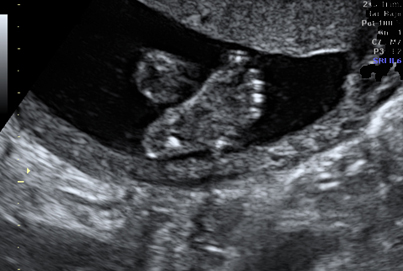

Ecografía de primer trimestre (semanas 11-14). Su objetivo básico es identificar el número de fetos (gestación única o múltiple), su vitalidad (latido cardíaco) y su tamaño (mediante la longitud cráneo-caudal). Durante esta ecografía se determinan una serie de parámetros que determinan un riesgo determinado para síndrome de Down y otras patologías cromosómicas, como la translucencia nucal, el hueso nasal o el flujo sanguíneo fetal. Estos datos se tienen en cuenta para informar sobre el riesgo de síndrome de Down (denominado screening combinado de cromosomopatías).